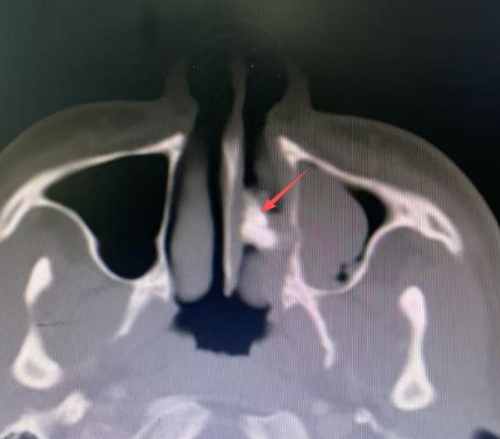

接诊的杨中纯副主任医师为李可进行鼻内镜检查时发现,其左侧鼻腔底部有一处呈粉色肉芽状的隆起,肉芽底部质地偏硬,呈现出沙砾样变化,表面并不光滑。与此同时,医生还检查了李可的口腔,奇怪的是,他口腔内牙齿完好,且并无严重的鼻部外伤史。这个“硬家伙”究竟是什么呢?为进一步揭开谜团,医生为李可进行了鼻腔CT检查。结果令人大吃一惊,这个困扰他多年的“鼻内硬物”——竟是一颗鼻腔异位牙!

箭头所指的就是鼻腔异位牙